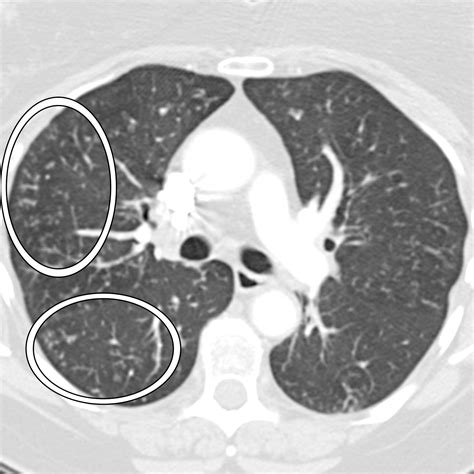

Laboratory tests, such as nasal swabs or rapid antigen tests, can confirm the presence of RSV. Chest X-rays may also be used to assess the extent of lung involvement. Accurate diagnosis is crucial for appropriate treatment and management.